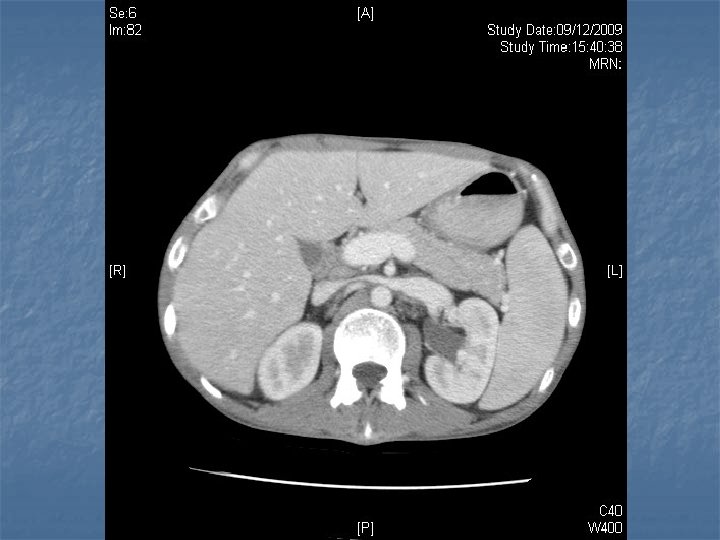

n n n PRETREATMENT INVESTIGATIONS: FBC, Renal and liver function, LDH, urate, Ig. GS. Histology review. Marrow aspirate+trephine (cytogenetics, immunology) CD 4 , HIV viral load. CT Scans. (MR Brain) (PET scan ) Echo / LVEF CMV, Hep B+C, Toxoplasma serology MAI screen. LP for CSF cytology +/- intrathecal Rx. (DLBC , Burkitt, Plasmablastic).